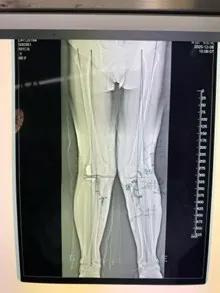

经过详细的体格检查、影像学评估和三维重建,医疗团队确认鲍奶奶的情况非常适合进行膝外侧单髁置换术。这种微创手术创伤小、恢复快,能够最大程度保留膝关节的自然结构和功能。

手术当天,骨科团队采用微创切口,仅约8厘米,远小于传统全膝关节置换手术切口。术中精准定位,仅置换病变的膝关节外侧间室。

手术使用了最新的单髁假体系统,这种假体设计更符合人体工程学,能够更好地恢复膝关节的自然运动轨迹。

整个手术过程仅持续约1小时,术中出血不到100毫升。术后鲍奶奶被送回病房,生命体征平稳。